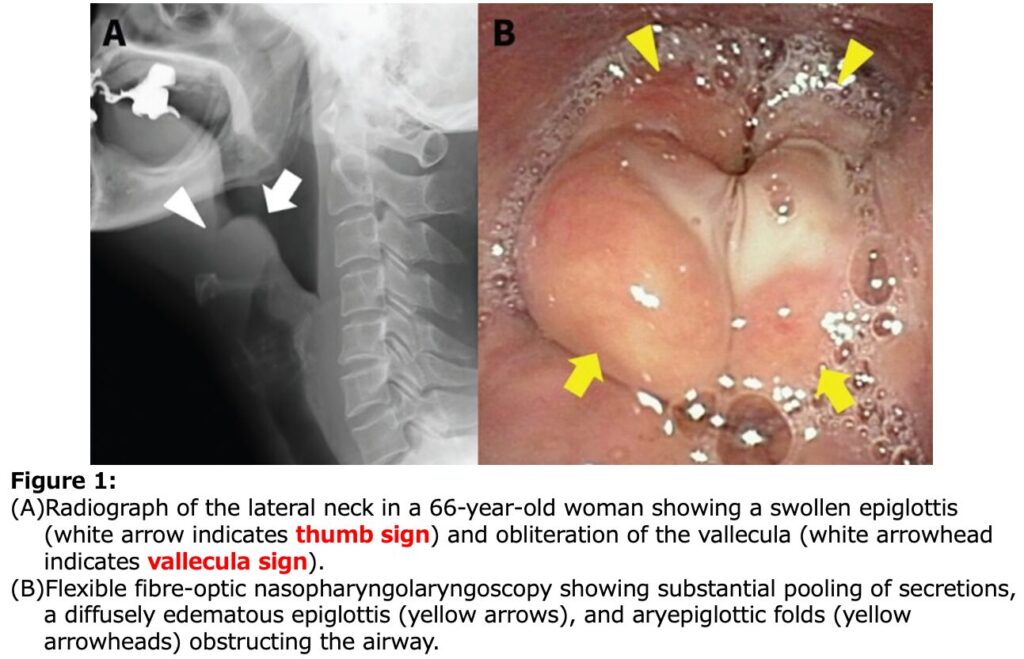

頸部側面X線撮影

- 急性喉頭蓋炎を疑う際の頸部側面X線撮影における各所見の感度と特異度は以下の通りです。

- thumb sign(広く丸い喉頭蓋):感度 65.9~66.7%、特異度 94.0~100%

- vallecula sign(喉頭蓋谷の消失):感度 53.9~71.4%、特異度 88.1~100%

- 喉頭蓋幅>6.3 mm:感度 75.8%、特異度 97.8%

- これらのX線画像所見は、急性喉頭蓋炎の診断において基本となる喉頭ファイバー検査(喉頭蓋の腫脹や発赤の直接確認)の実施が困難な場合に有用とされています。